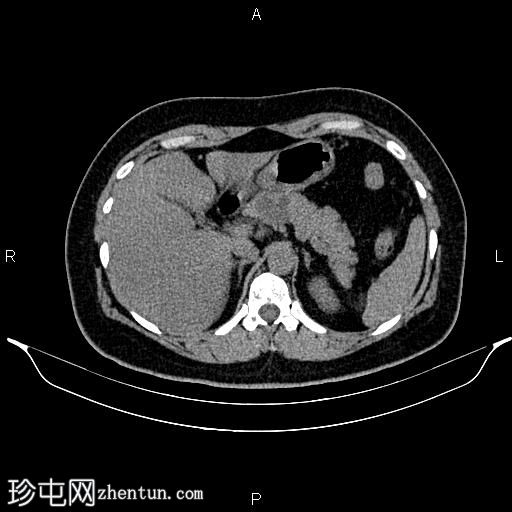

轴位增强扫描

门静脉期

胰体近端可见一大小为32 × 27 mm的分叶状微囊性肿块,内部可见强化分隔,无明显钙化。胰腺其余部分未见异常,胰管未见扩张。

肝脏密度值低于脾脏,提示脂肪肝。

影像学上,胰腺浆液性囊腺瘤通常表现为胰头多囊性、分叶状肿块,形似一串葡萄。约20%的病例可见特征性的强化中央瘢痕,该瘢痕可伴有星状钙化。